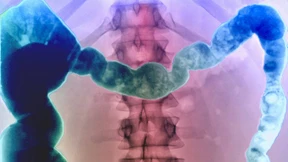

Fibromyalgie galt lange als ein rein psychisches Leiden. Neue wissenschaftliche Ergebnisse zeigen, dass das zu kurz greift. Doch woher kommt der Schmerz?

„Reizdarmsyndrom“ ist ein Begriff für ein schweres Krankheitsbild, dessen Ursache noch nicht vollständig geklärt ist. In die „Psychoecke“ stellt man die Betroffenen aber heute nicht mehr.